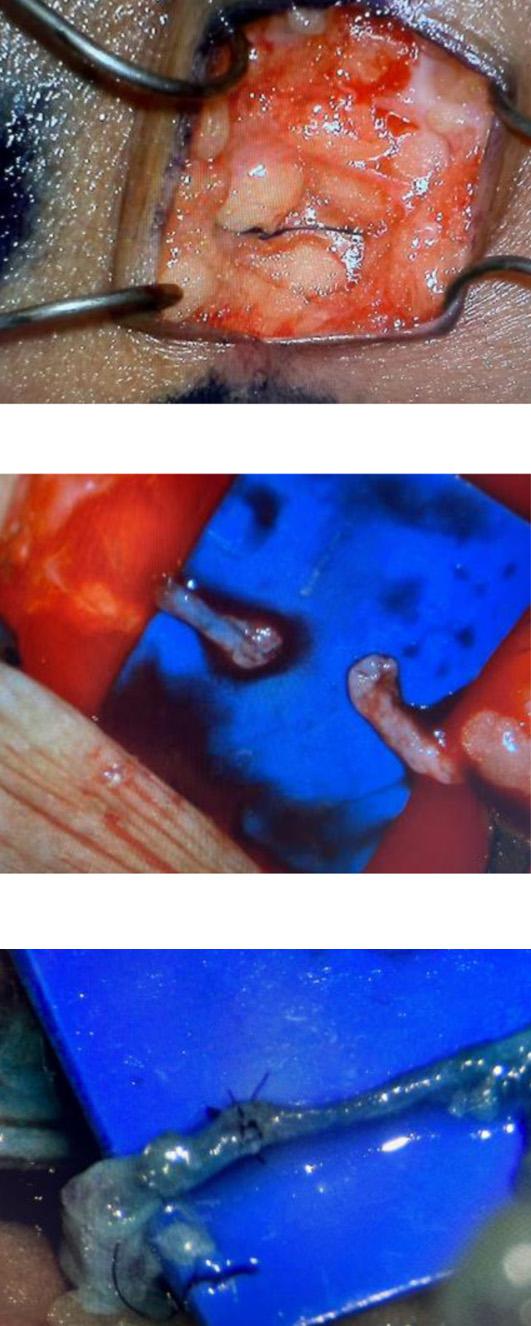

Se efectuó la derivación linfático-venosa múltiple proximal y distal. Se realiza anastomosis linfático-venosa múltiple con un total de 9 derivaciones (Fotos 11-14), con utilización de super microcirugía, mediante incisiones en piel de 2 a 3 cm de longitud, con una visualización previa en linfo-resonancia y ecografía de vasos linfáticos, con un promedio del tamaño de los linfáticos de 0,1 mm a 0,4 mm y con vénulas de 0,3 mm a 0,6 mm. Además de confirmación intraoperatoria de linfáticos con azul de metileno (Foto 15). A las 18 horas del procedimiento, el débito de la quiloascitis bajó a 18.000 cc al día, llegando a la producción de 1.500 cc al día para el sexto día posquirúrgico. Diez días después de la cirugía se retiró el dren (Foto 13) y posteriormente se le dio egreso hospitalario a la paciente. En la consulta de seguimiento de 1 mes posoperatorio se encontró un abdomen sin ascitis, sin salida de secreción por heridas, blando y depresible. Finalmente, en el seguimiento de un año, la paciente sigue sin ascitis y sin síntomas abdominales (Fotos 14-21).